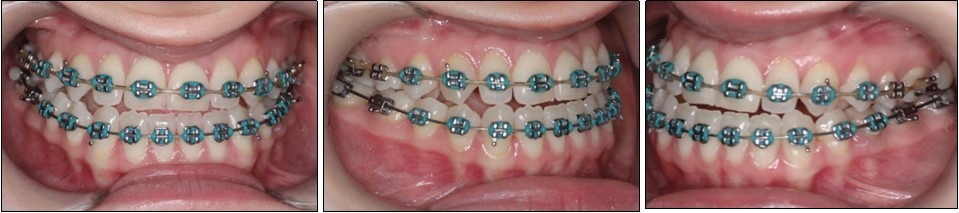

The pre-surgical orthodontic preparation successfully met the following objectives: levelling and aligning, flattening of curbe of Spee, proclination of the lower incisors and elimination of dental compensations. Before surgery, the patient had a normal position of the lower incisors, with IMPA 88 degrees. (Figure 4) Before surgery, a slight anterior open bite and an anterior crossbite could be observed, due to the elimination of dental compensations. Crimpable hooks were placed between each tooth on the 0.019x0.025 SS archwires, to allow placement of intermaxillary elastics after surgery. (Figure 5).

Figure 5.Pre-surgical intraoral photographs